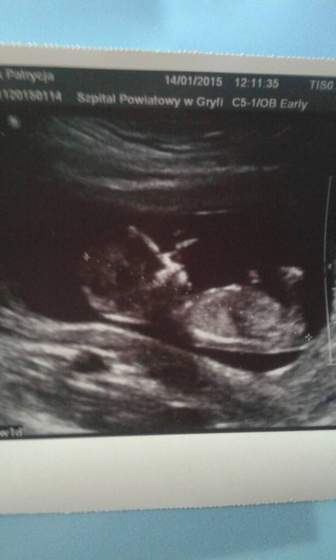

patka :-) mnie to na chłopaka wygląda! Sterczą tam jakby dwie antenki,nawet jak pierwsza to pępowina,to pod nią też coś jakby sterczy do góry. :-) super by było!

Ale ja to tylko okiem laika oceniam,bo się nie znam zupełnie.

patka90 jeśli to co widzę to zarys nuba, to wygląda mi również na chłopca

Patka ja mam takie samo zdanie jak liski i vviedzma nub chlopczykowy jak dla mnie

Patka - ja się nie znam, ale tak na pierwszy rzut oka wygląda Twój dzidziuś na chłopczyka

Patka dla mnie też dzidziuś wygląda na chłopczyka :-)